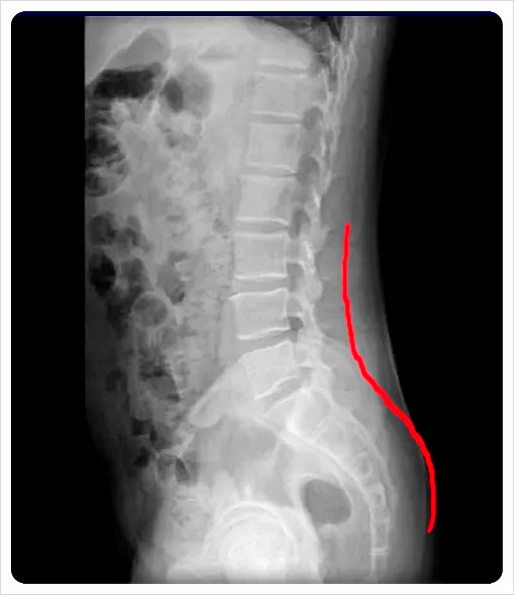

전방 경사는 골반 앞쪽이 아래로 내려가고 뒤쪽이 올라간 형태, 후방 경사는 그 반대로 뒤쪽이 내려간 상태를 말합니다.

오래 앉아 있는 습관, 엉덩이 근육 약화, 허리 과사용과 밀접한 관련이 있습니다.

허리가 자주 뻣뻣하거나 엉덩이가 쉽게 뭉친다면 이미 전후방 경사가 어느 정도 진행된 상태일 수 있습니다.

허리 전만·후만 변화